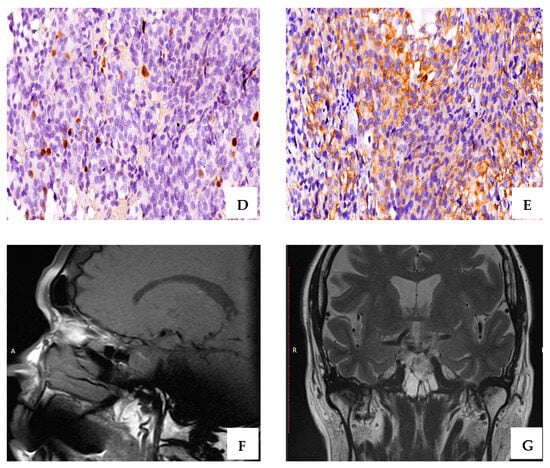

2.3. Immunohistochemistry Evaluation

4.1. Histopathological Exam

4.2. Immunohistochemical Staining

4.3. Scoring of Immunohistochemical Stains